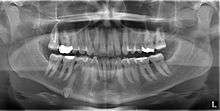

An impacted tooth is one that fails to erupt into the dental arch within the expected developmental window. Because impacted teeth do not erupt, they are retained throughout the individual's lifetime unless extracted or exposed surgically. Teeth may become impacted because of adjacent teeth, dense overlying bone, excessive soft tissue or a genetic abnormality. Most often, the cause of impaction is inadequate arch length and space in which to erupt. That is the total length of the alveolar arch is smaller than the tooth arch (the combined mesiodistal width of each tooth). The wisdom teeth (third molars) are frequently impacted because they are the last teeth to erupt in the oral cavity. Mandibular third molars are more commonly impacted than their maxillary counterparts. As a general rule, all impacted teeth must be removed,[1] except canine teeth; canines do not need surgery and may just remain buried and give no further problems.[2]

Classifications enable the oral surgeon to determine the difficulty in removal of the impacted tooth.[3] The primary factor determining the difficulty is accessibility, which is determined by adjacent teeth or other structures that impair access or delivery pathway. The majority of classification schemes are based on analysis on a radiograph. The most frequently considered factors are discussed below.

Most commonly used classification system with respect to treatment planning. Depending on the angulation the tooth might be classified as: